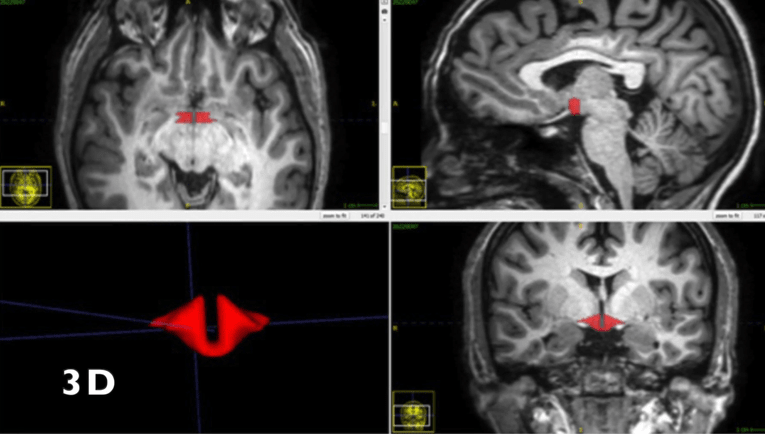

Chodzi o podwzgórze, które odpowiada m.in. za hormonalną regulację temperatury ciała, tętna, nastroju, apetytu, popędu seksualnego i snu - podał serwis Towarzystwa Radiologicznego  Północnej Ameryki (rsna.org).

Badania przeprowadzono na grupie 50 zdrowych kobiet, z których 21 używało doustnej antykoncepcji. Badano je za pomocą magnetycznego rezonansu jądrowego (MRI) oraz nowych, opracowanych przez autorów metod analizy obrazu.